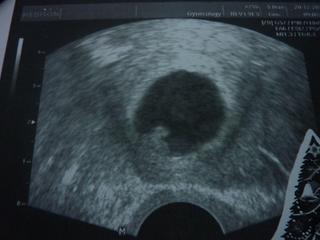

tak já dnes byla na kontrole, jsem 6+3tt a už mi dr. Slámová říkala, že tam je počínající srdeční akce a plůdek měří 3,3 mm. Jsem tak šťastná!!! Vím, že není vyhráno, ale strašně mě to uklidnilo. Už jsem se viděla na revizi.